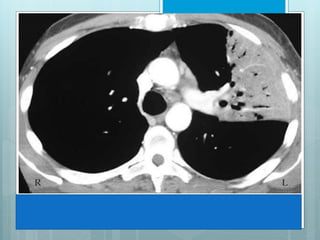

RLL Collapse

 Collapse is in post, med & inf

direction.

 Major fissure swings down

&backward.

 Hilum is displaced inferiorly.

 Hemidiaphragm is elevated.

 On PA view a triangular opacity

adjacent to spine with base on

hemidiaphragm.

 On lateral view there is

increased opacity over lower

thoracic vertebrae .

 Another indirect sign is vascular nodular sign, due to

compensatory hyperinflation of upper lobe.

 Radiographically seen as "hair-pin" turning of vessels &

"too-many nodules" along cardiac margin, which are end-on

vessels.